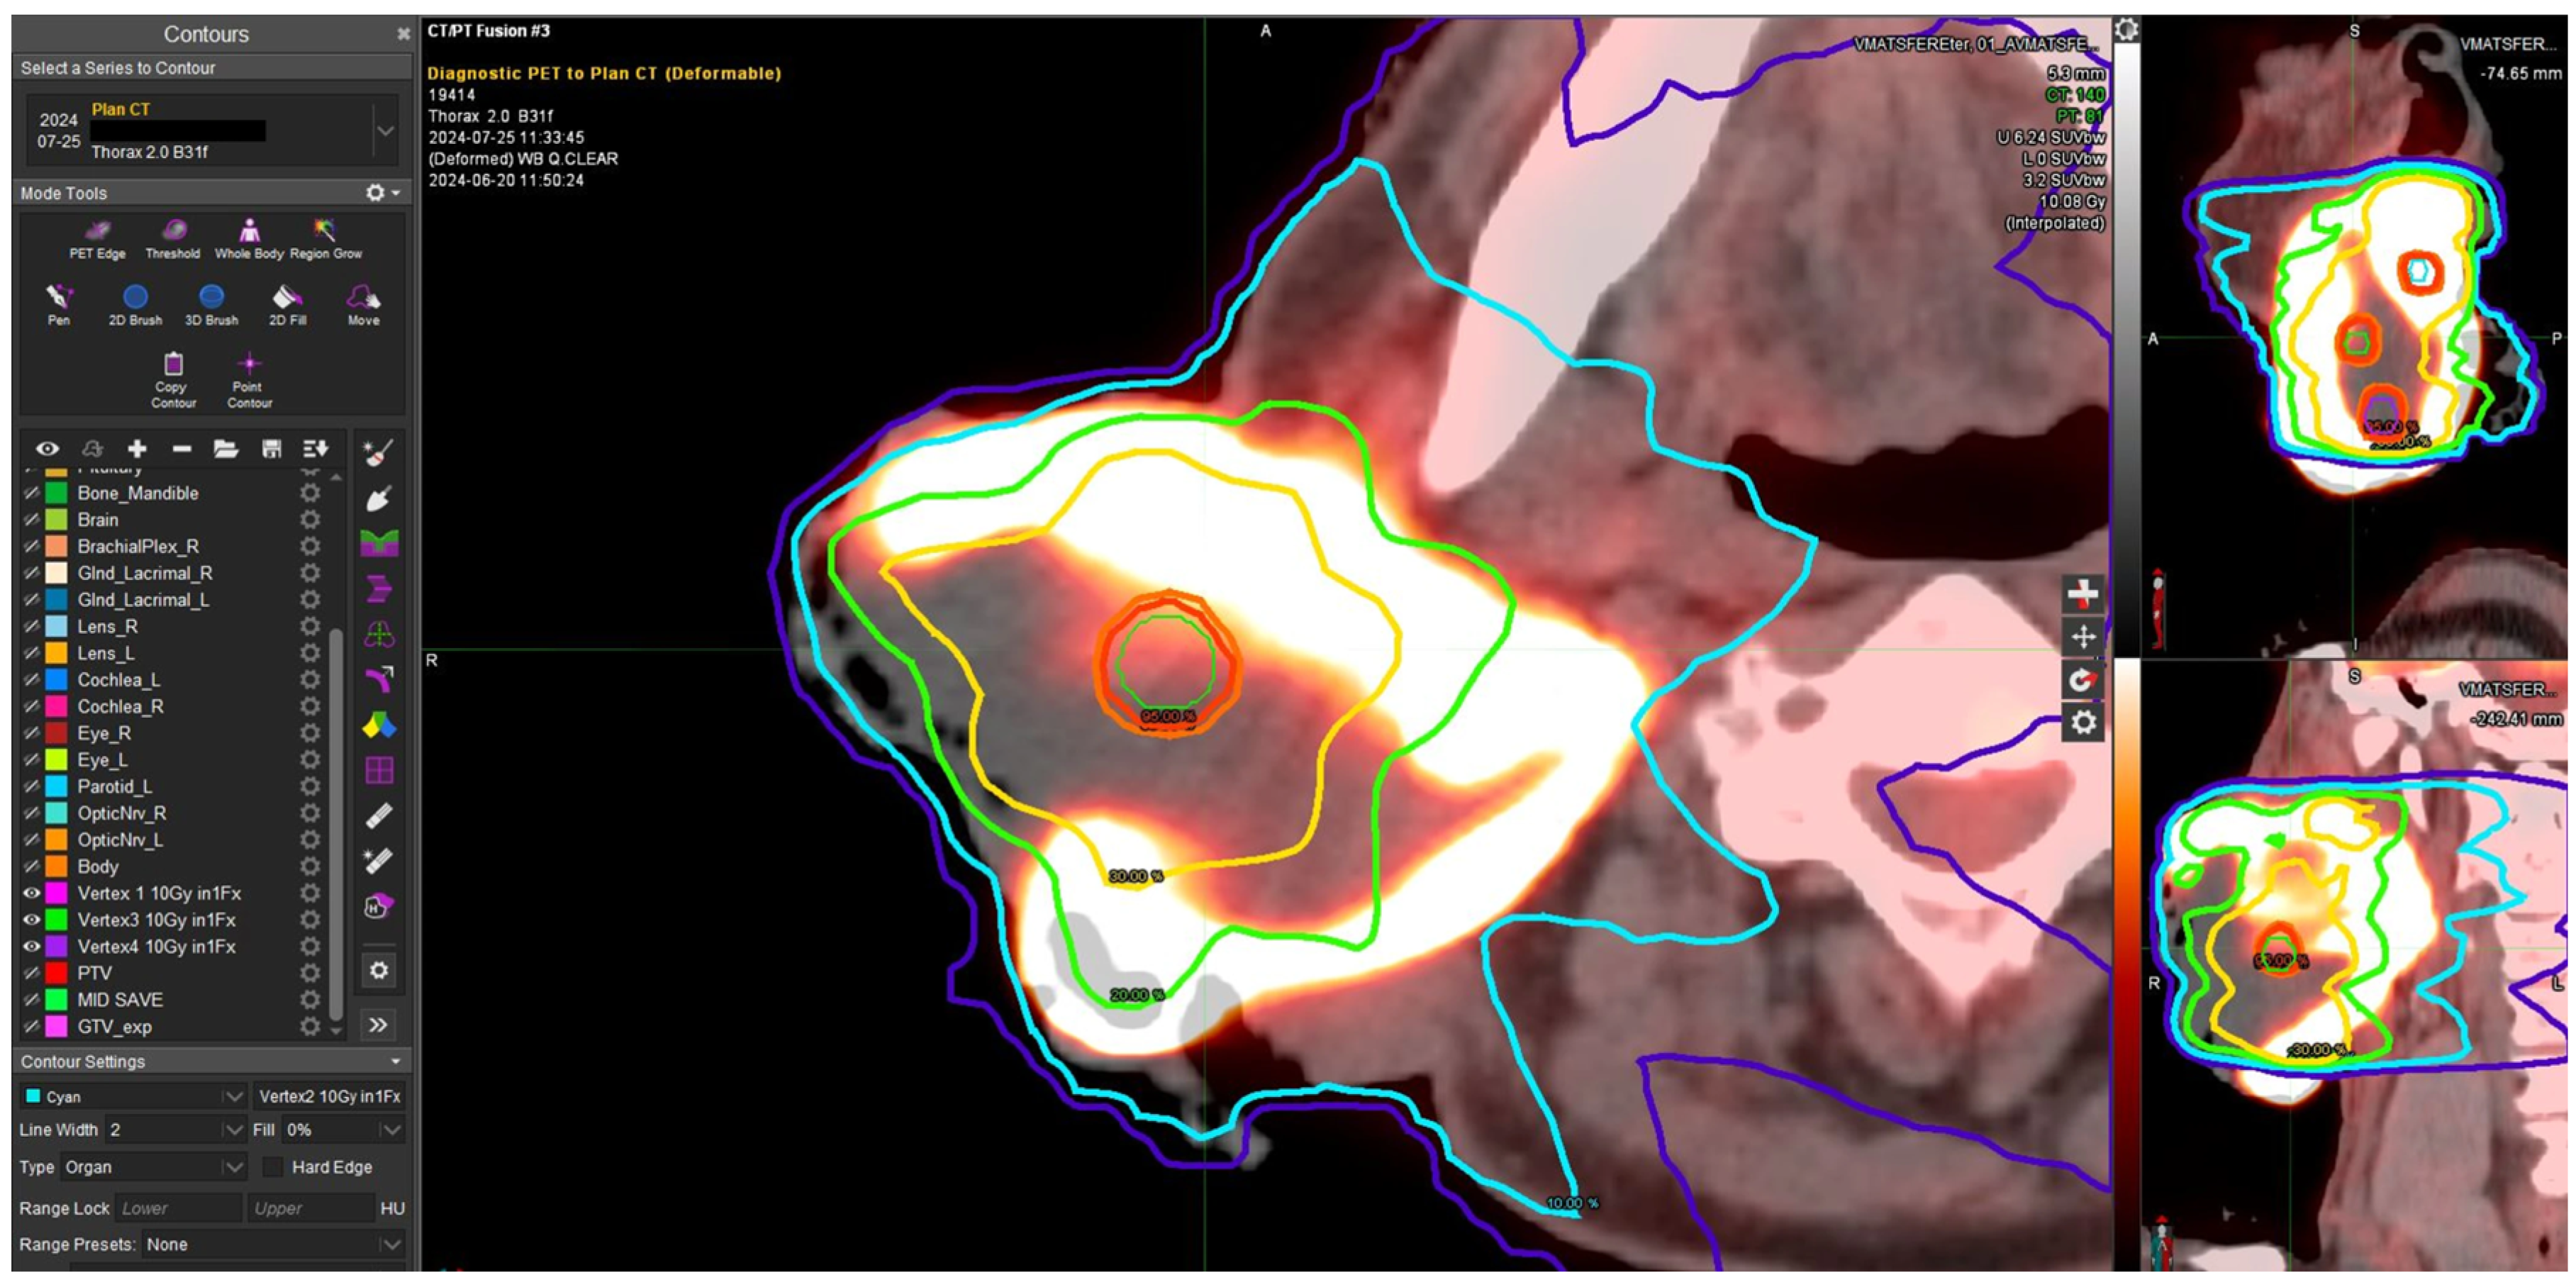

2.2. Plan Contouring and Treatment Criteria

2.3. Treatment Planning Setting

2.4. Dosimetric Evaluation